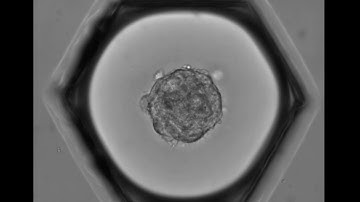

Spheroid-Migration of MSC in a PEG-Fibrinogen Hydrogel